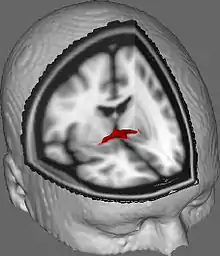

![]() Coronal cross-section of brain showing the anterior commissure. (left, third from bottom.) | |